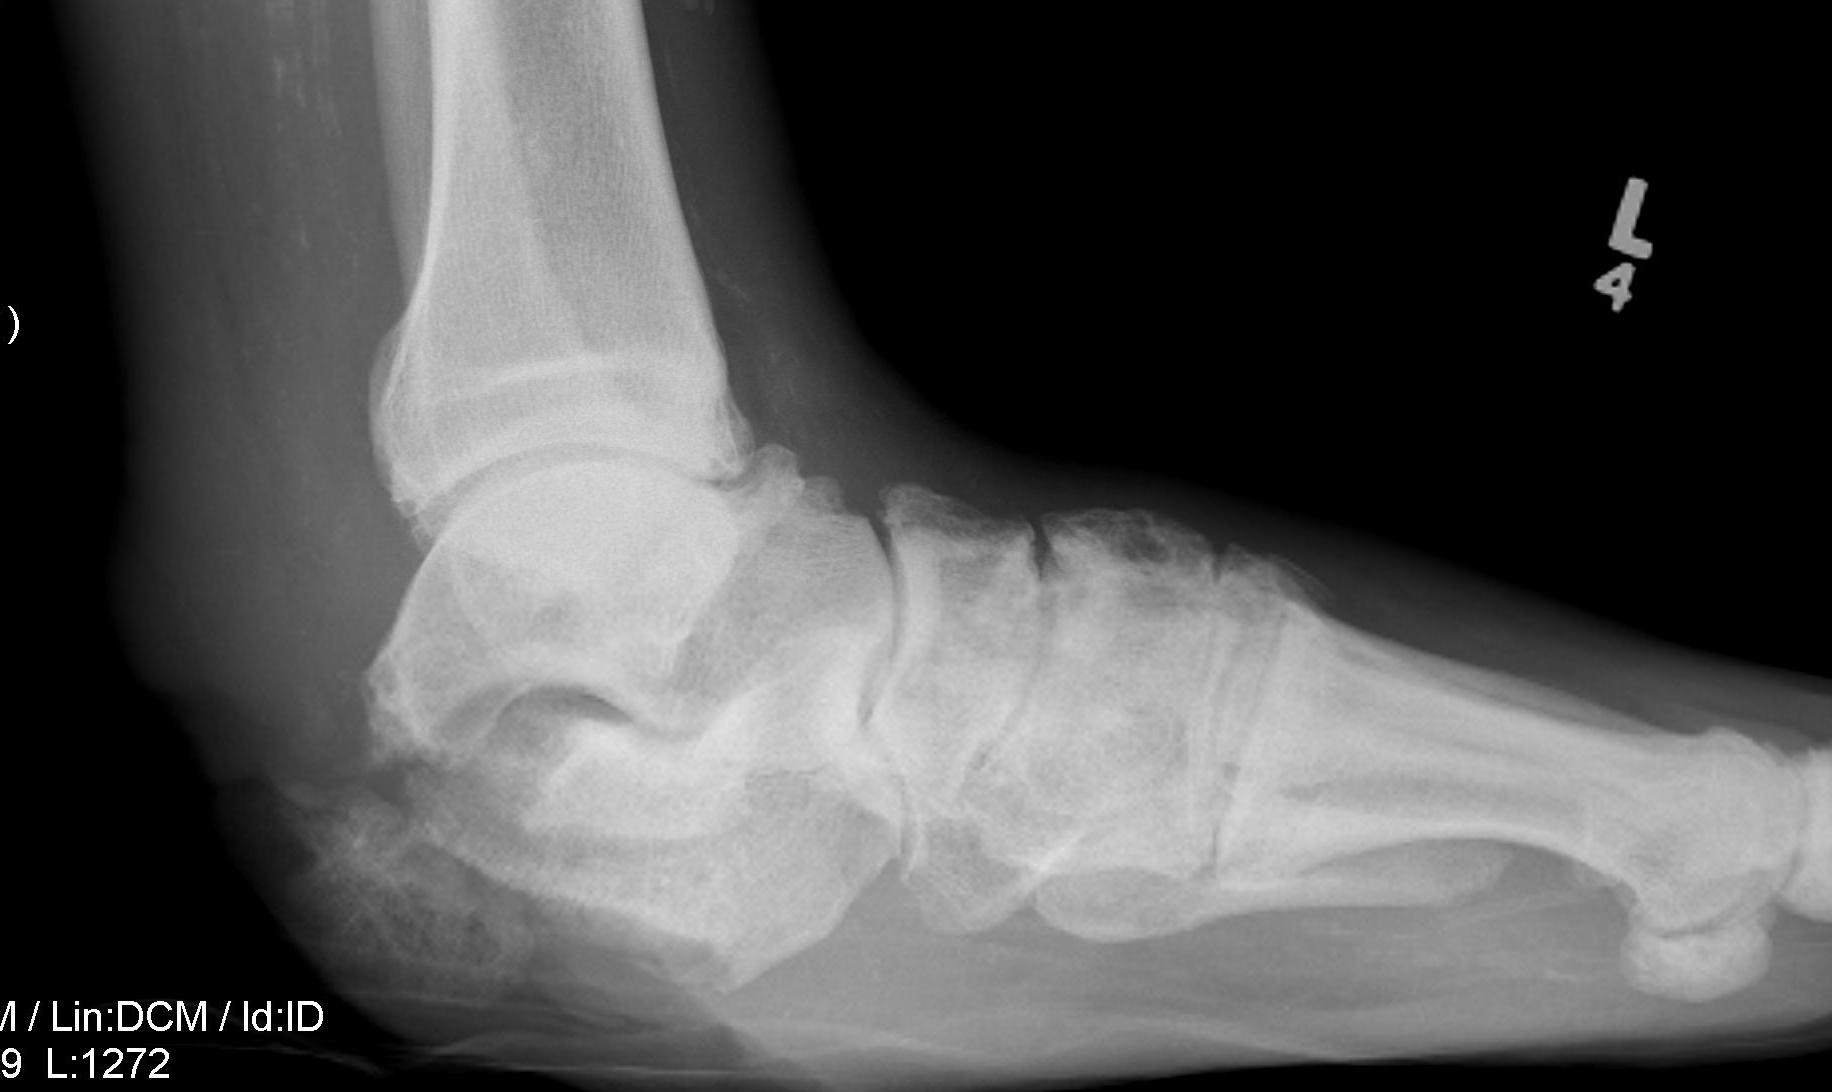

Charcot arthropathy

Midfoot ulcer with evidence of underlying Charcot arthropathy and midfoot collapse

www.boneschool.com/charcot-foot